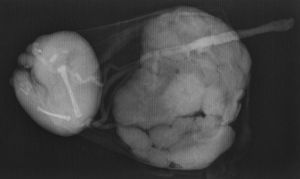

Nace un feto sano, varón, de 2.615 g, con un Apgar de 6/10, y se obtienen una placenta y una masa compatible con feto acardio de 192 g y una única placenta que se envían al servicio de anatomía patológica. Previamente se realiza una radiografía (fig. 1), donde se visualizan huesos largos que remedan a la tibia y al peroné.